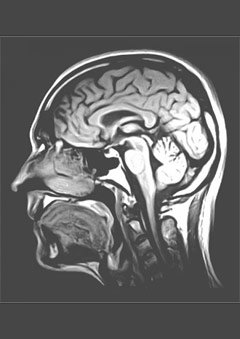

unidentified or unknown. Usually the diagnosis comes after examination by a

neurologist, which includes a physical exam, family history, MRI scanning of the

brain and spine, and spinal tap.